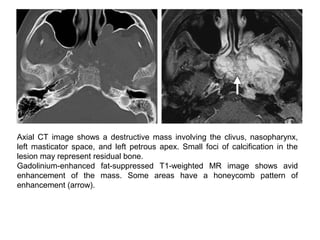

Axial CT image shows a destructive mass involving the clivus, nasopharynx,

left masticator space, and left petrous apex. Small foci of calcification in the

lesion may represent residual bone.

Gadolinium-enhanced fat-suppressed T1-weighted MR image shows avid

enhancement of the mass. Some areas have a honeycomb pattern of

enhancement (arrow).